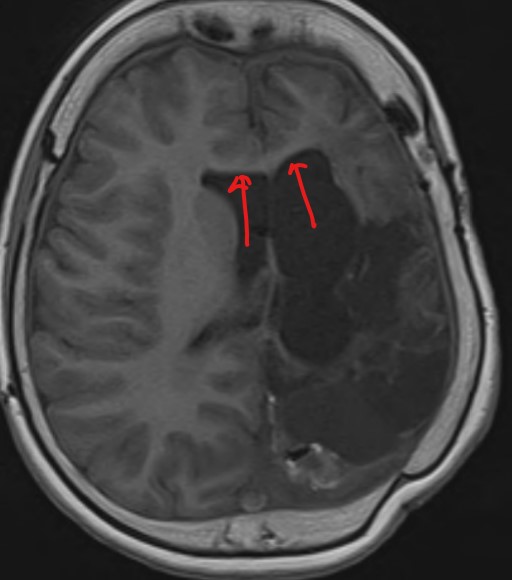

The above page, represented on bipolar montage:

While there is an asymmetry of beta frequencies on the common average montage, especially over the central-parietal regions, the asymmetry is easily missed. The bipolar montage demonstrates suppression of normal rhythms over the left hemisphere; the suppression over the left hemisphere cannot be appreciated on the referential montage. The EEG has been performed on a patient who has previously had a left hemispherectomy.